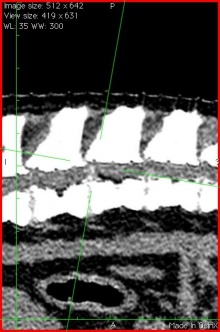

神経学的検査である程度異常が疑われる場所を特定しておいて、それをCTで確認します。思った通りの場所に椎間板の脱出が見られ、手術で大量の椎間板物質を摘出しました。手術はうまくいきましたから、たぶん歩けるようになってくれると思います。